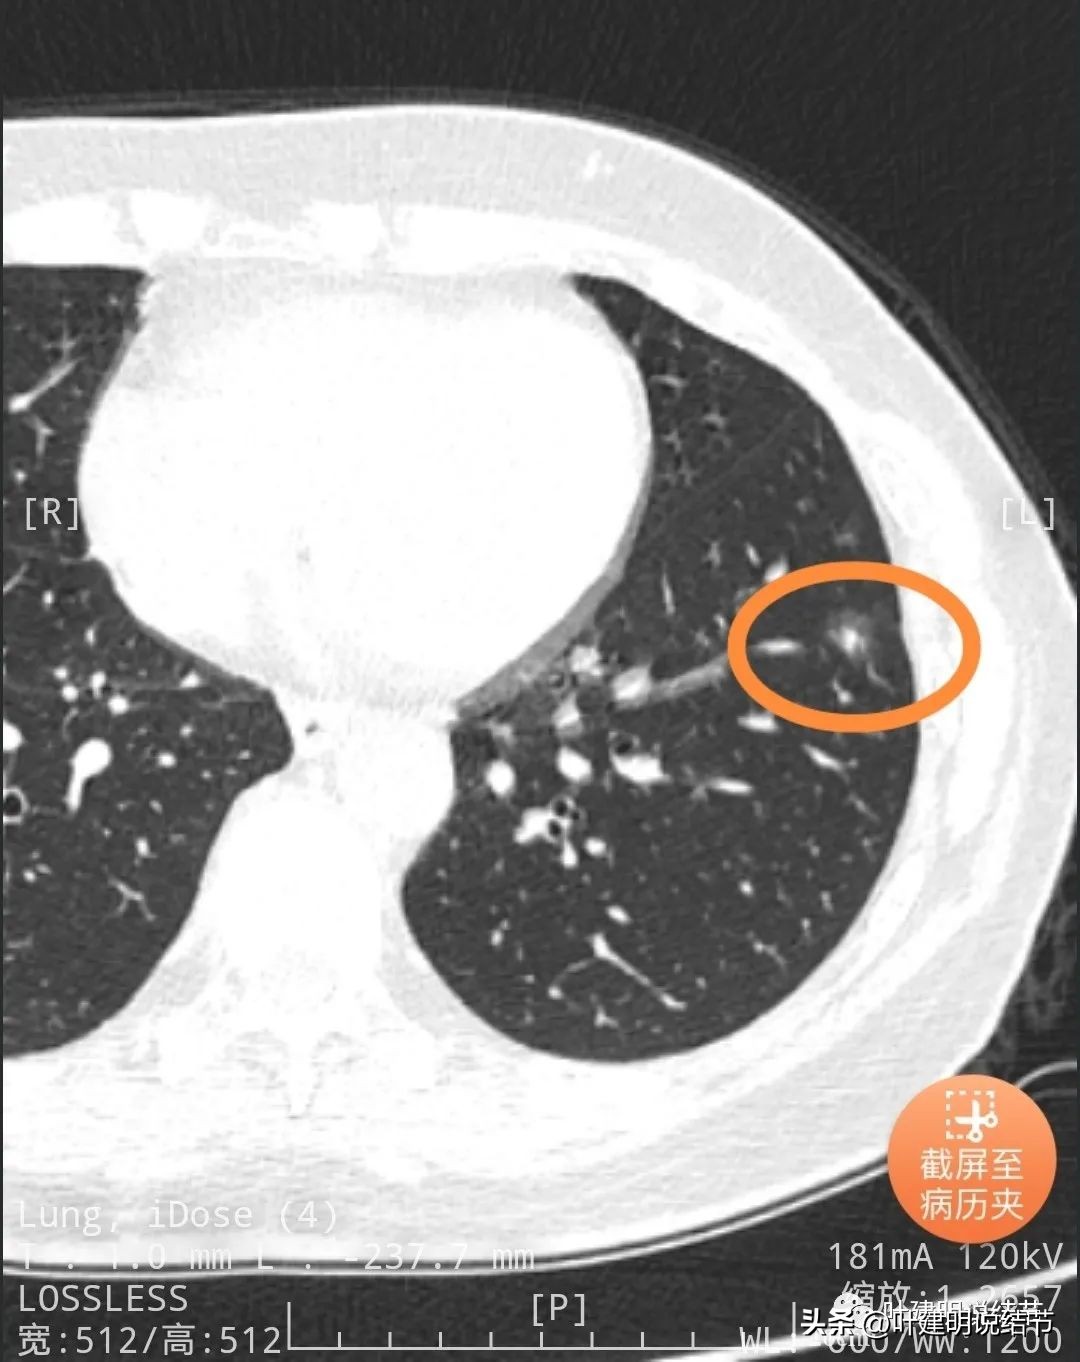

靶重建后发现病灶囊腔型,桔色箭头示进入的血管有异常增粗,而且壁显得毛糙;黄色箭头示空腔;红色箭头示整体轮廓较清;绿色箭头示有磨玻璃成分,虽然密度较低;蓝色箭头示病灶略有胸膜牵拉影响,只是力较弱而已。

上图显示了病灶轮廓与瘤肺边界其实还是清楚的。

部分边缘有毛刺征可见。

显示明显的血管征与血管异常增粗和壁毛糙。

上图显示病灶轮廓较清,有锐利细毛刺征,灶内有弯曲血管穿行。

囊壁有少许是偏实性成分的,如粉色箭头所示。

血管增粗进入并散开来。

血管在病灶内发出分支。